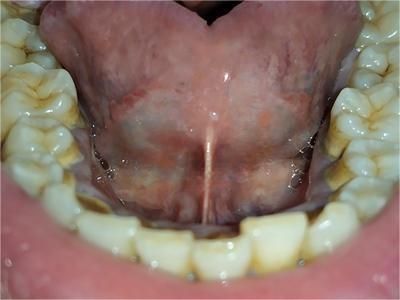

舌系带过短是一种先天发育异常,由于舌系带在舌腹部的附着点前移至舌尖或接近舌尖,或牙槽嵴附着点上移至牙槽嵴上部,或者附着点正常,系带本身过短可引起该症状。

随着牙齿萌出,牙槽嵴的发育和舌的不断运动,舌系带附着点会随之逐渐退降,舌系带也会随之不断地松弛增长。如果下前牙已萌出,因舌系带过短引起系带溃疡,应早期手术治疗,手术包括舌系带切断术、舌系带延长术等。